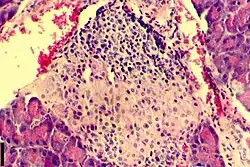

Insulitis

Als Insulitis wird in der Medizin eine entzündliche Infiltration von Zellen des Immunsystems in die Langerhans-Inseln der Bauchspeicheldrüse (Pankreas) bezeichnet. An einer Insulitis sind vorwiegend CD4-positive T-Lymphozyten beteiligt, darüber hinaus spielen antigenpräsentierende Zellen wie Makrophagen und dendritische Zellen sowie in geringerem Maße B-Lymphozyten und CD8-positive T-Zellen eine Rolle. Zu den für eine Insulitis relevanten pro-inflammatorischen Zytokinen zählen insbesondere IL-1β, TNF-α und IFN-γ.

Das Auftreten einer Insulitis ist durch pathologisch-histologische Untersuchungen sowohl bei Patienten mit neu manifestiertem Diabetes mellitus im Kindesalter (Typ-1-Diabetes) als auch bei entsprechenden Tiermodellen dieser Erkrankung wie der BB-Ratte und der NOD-Maus dokumentiert. Sie ist deshalb höchstwahrscheinlich ein Prozess mit einer zentralen ursächlichen Rolle beim Untergang der insulinproduzierenden Betazellen in den Langerhans-Inseln, der zu einem Typ-1-Diabetes führt. Die genauen Abläufe, die zur Entstehung dieser Diabetes-Form beitragen, sind jedoch ebenso wie die Ereignisse, die eine Insulitis auslösen, bisher nicht im Detail aufgeklärt worden. Als mögliche Ursachen einer Insulitis werden unter anderem Virusinfektionen und andere Umweltfaktoren diskutiert.